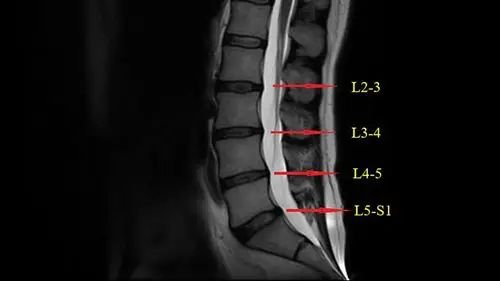

那么腰椎位置分别受压后会有什么表现呢?